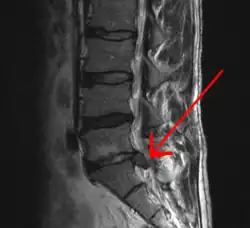

| Imagem de RNM de hérnia de disco lombar (seta) | |